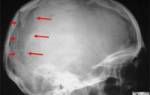

Последствия гидроцефалии

На ранних стадиях гидроцефалию легче вылечить и избежать ее опасных последствий, чем на запущенных.

Водянка нарушает кровоснабжение тканей головного мозга, что приводит к необратимой атрофии (см. фото выше).